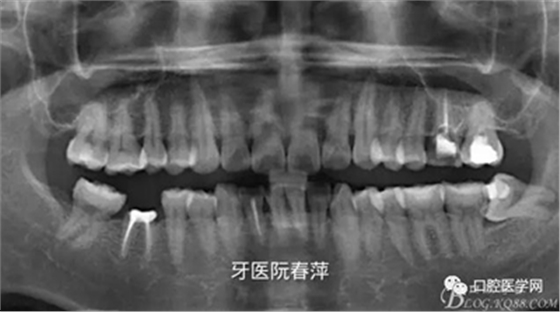

(5)X光片檢查:全景片看到25齲壞未近髓,26根管充填材料良好,27根管無充填材料,根尖區(qū)未見低密度影。

全景片如下圖

絢彩AT無飾瓷全形態(tài)氧化鋯產(chǎn)品體驗(yàn)+全冠和嵌體微創(chuàng)修復(fù)后牙當(dāng)時(shí)25和27無臨床癥狀均無做任何處理。由于考慮到26的牙體破壞面積大,固位抗力不佳,根管治療后纖維樁加固樹脂充填。